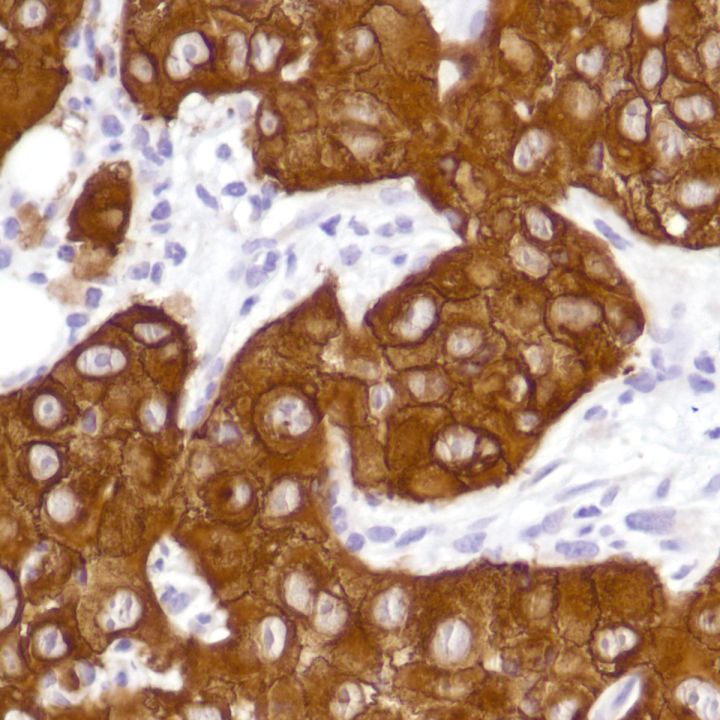

Epidermal Growth Factor Receptor (EGFR) (E746-A750del) (SP111)

EGFR is a transmembrane tyrosine kinase that belongs to the HER/erbB protein family. Somatic mutations in the tyrosine kinase domain of EGFR are present in a subset of lung adenocarcinoma. Two types of mutations account for approximately 90% of mutant cases: a specific point mutation L858R which occurs in exon 21 and short in-frame deletions in exon 19. A common lesion in exon 19 is the deletion of E746-A750, although other variants can also occur.